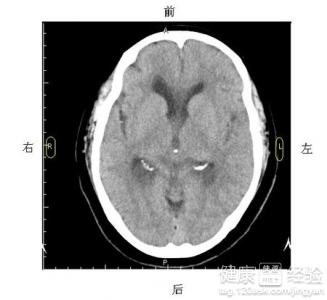

剛出生的早產兒,很多醫院一遇到問題就要求去做腦部CT,但是腦部CT對嬰兒是否有影響呢?很多新手爸爸媽媽都很擔心,都很糾結是否給寶寶做,做了吧,擔心有輻射,不做吧,又擔心病會影響到以後的神態。我根據個人的經驗,為了排除別的毛病還是做比較放心,而且做個一兩次也沒有多大影響的,在檢查的時候需要注意什麼呢,現在根據我的情況分享一下經驗。

1我家寶寶是早產兒,一出生幾天,醫生就建議做一下腦部CT,查看是否缺氧。由於寶寶太小了,在檢查的時候肯定會亂動的,不會配合醫生檢查。所以在檢查前(待診時)最好要寶貝入睡,一般小的時候娃都愛含著乳頭入睡的。

3為了將輻射降到最低,可以要求醫生為寶寶做好輻射防護,為您也做好充分的防護措施,這樣就可以將輻射損害降至最低了。並且檢查完了,馬上出來。有的人在裡面逗留很久,這些都是不好的。

一般醫生建議做腦部CT,主要是看早產兒是否缺氧,為了確診,做一下腦部CT還是有必要的,雖然是有輻射,但是為了孩子的長遠考慮,絕對有必要去做腦部CT。不要一味的認為有輻射就堅決不做,醫生還是比較專業的,中國的不良醫生有,但是要相信還是有很多好醫生的。